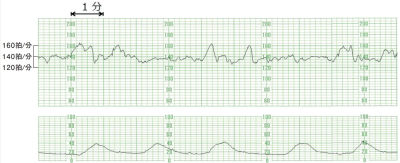

来院時の腟鏡診で淡血性の帯下を少量認めた。内診で子宮口は閉鎖していた。腹部超音波検査では胎児は頭位で形態異常はなく、推定体重は 1,850 g、胎盤は子宮底部に付着し、羊水指数<AFI>は 18.0 cm であった。胎児心拍数陣痛図及び経腟超音波像を別に示す。